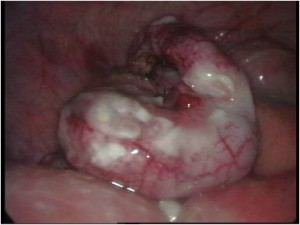

Acute scrotum is sudden onset of redness and swelling over the scrotum. This is associated with severe pain over the scrotum and sometimes lower abdomen and may be accompanied with nausea and vomiting.

Of the many causes of acute scrotum, the most common and important is Torsion of Testis. The testis is supplied by a single blood vessel and any torsion on this vessel may impede the blood supply to the testis. If urgent medical attention and intervention is not done, this may result in testicular gangrene and orchidectomy ( removal of the dead testis) may be needed.

The commonly misleading history given by the parents is that the child may have had a trivial trauma or an insect bite. However, for the clinician the golden rule should be ‘Any acute scrotum is testicular torsion unless proved otherwise’. Investigations like ultrasound and color doppler may be done to help in the diagnosis. However, in the event of any doubt, it is safest to do a surgical exploration of the scrotum. The other uncommon causes of acute scrotum are acute epidydymo orchitis, scrotal abscess, idiopathic scrotal oedema and torsion of appendix of the testis. ●

Acute Scrotum

Torsion Testis (Pre and Per operative photo)